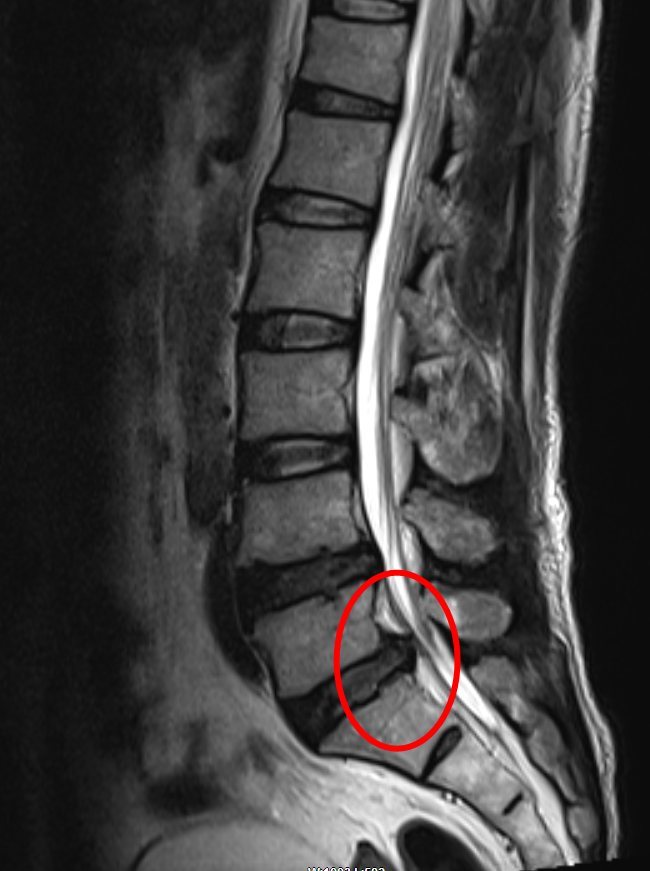

▼術前

從檢查結果看,周先生有很大一塊椎間盤組織脫垂了出來,并壓迫到了神經(jīng),導緻由坐骨神經(jīng)支配的整個右側腰、腿出現比較嚴重的反射痛和麻木感,緻使周先生行走不便,嚴重影響周先生的日常生活、降低了其生活質量。因此脊柱外科建議周先生進(jìn)行經(jīng)椎間孔鏡下髓核摘除術,爲周先生的神經(jīng)根進(jìn)行減壓。